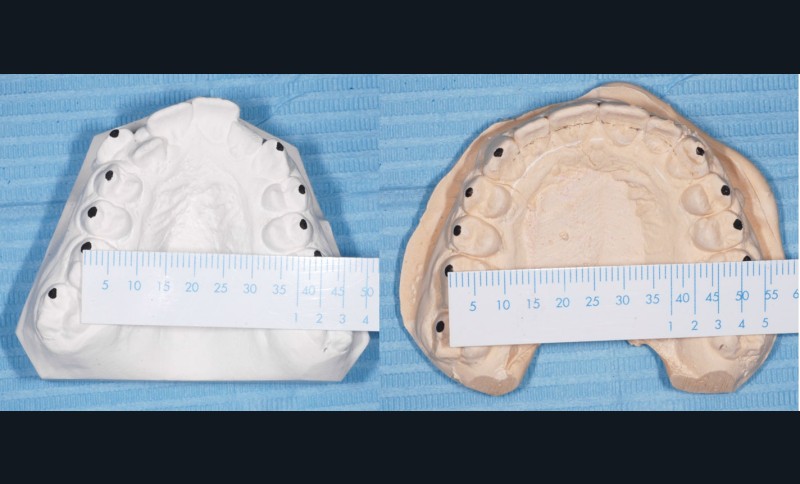

Sans aucun appareillage d’expansion, le maxillaire a été transformé et semble avoir été soumis à une disjonction (fig. 30).

Les moulages avant-après montrent une augmentation du sens transversal de 10 mm au niveau des 1re et 2e prémolaires (fig. 31).